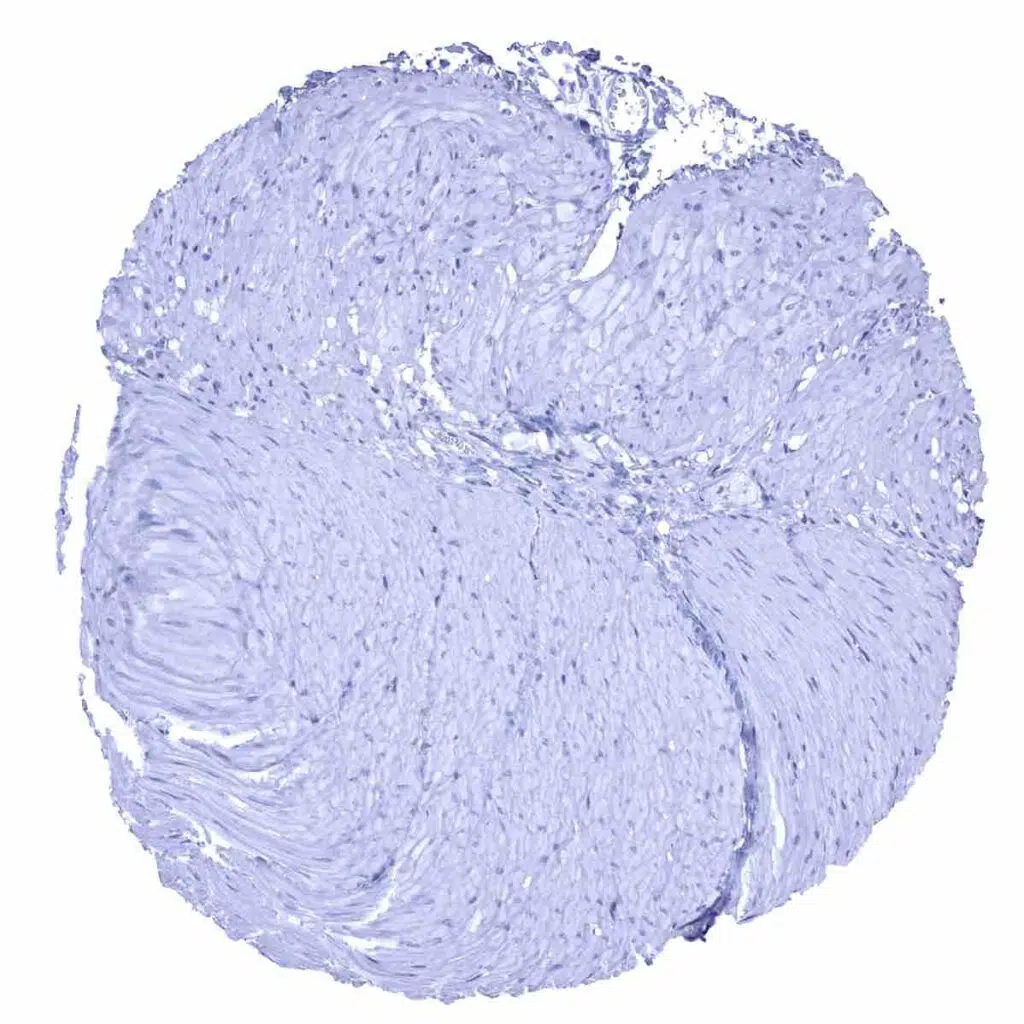

Uterus, myometrium